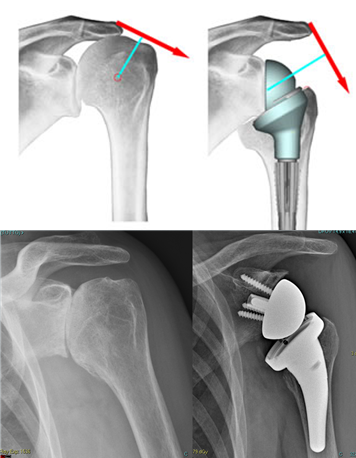

Advanced degenerative-arthritic diseases of shoulder and elbow are treated by prosthetic replacement with the aim of providing pain free movement in elderly patients or in younger patients with severe post-traumatic joint diseases.

In the latest years, articular shoulder and elbow prostheses intensely developed, with always more “anatomic” designs (that is, systems that are similar to the anatomy of the healthy joint).

The continuous research in minimally invasive and new materials development allow us, when indicated, to use implants with short stem or pyrocarbon surfaces, solutions that allow to better respect the patient's anatomy and the osteo-cartilaginous structures of the shoulder, with the aim to speed up the post operative recovery and reduce the possible complications.

Patients with an irreparable rotator cuff tear (who, until recently, have been severely limited in their activities) can today be treated with the so-called “inverse prosthesis”, which is based on the inversion of the articular surfaces shape.